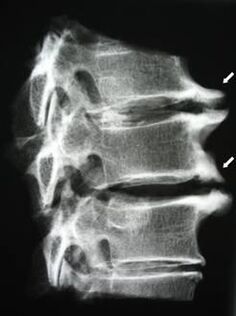

U početnim fazama osteokondroza se otkriva pomoću MRI. Kasnije se patologija može dijagnosticirati pomoću radiografije. Na rendgenskim snimkama vratne kralježnice uočava se smanjenje razmaka kralježaka, patološke promjene u fasetnim zglobovima i osteofitoza.